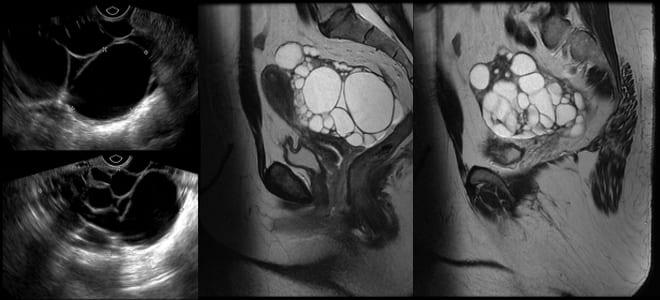

На ультразвуковом исследовании, магнитно-резонансной томографии и компьютерной томографии тератомы могут проявляться как однокамерные или двукамерные образования. В 60% случаев в их составе обнаруживается кальций. Внутри тератомы содержат жировую жидкость, вырабатываемую сальными железами.

Определить наличие тератомы на яичниках можно визуально, обратив внимание на эхогенные полосы.

Проведение МРТ и КР при диагностике кисты яичников

КТ и КРТ представляют собой высокоточные методы диагностики, которые позволяют выявить местоположение, размеры, характер и тип кисты.

Эти методы чаще всего применяются при подозрении на рак придатков. В процессе исследования пациентке вводят контрастное вещество, после чего она располагается в специальной капсуле, которая не герметична. Магнитно-резонансная терапия (МРТ) помогает установить, привело ли развитие злокачественной опухоли к образованию метастазов и, если да, то в каких участках они находятся.

КТ подразумевает получение дозы рентгеновского излучения. Этот метод используется для получения 2-мм срезов яичника, которые обрабатываются компьютером и формируют изображение.